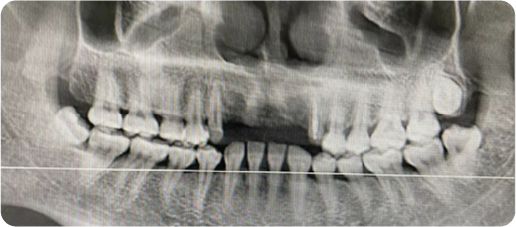

Multi-unit Dental Implant Case

BEFORE

VS

AFTER

Name:MS DengAge:31

Evaluation: Long-term use of a removable denture has led to compromised mastication and severe alveolar bone resorption.

Treatment Plan:The solution involves three dental implants that anchor a five-tooth bridge.Two artificial teeth are suspended between the implant-supported crowns, restoring all five missing teeth.

Patient Feedback:Tought&Feel like natural teeth.Unlike removable dentures, implant-supported teeth are designed for lasting comfort, security, and a natural appearance—without slipping or the need to grind down adjacent teeth.